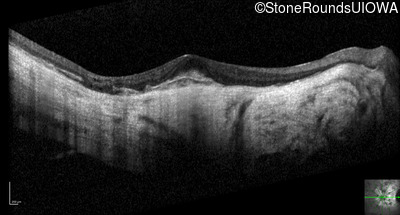

Optical Coherence Tomography - Right - 20/40 -2

Exemplar / OCT Stack

OCT Stack